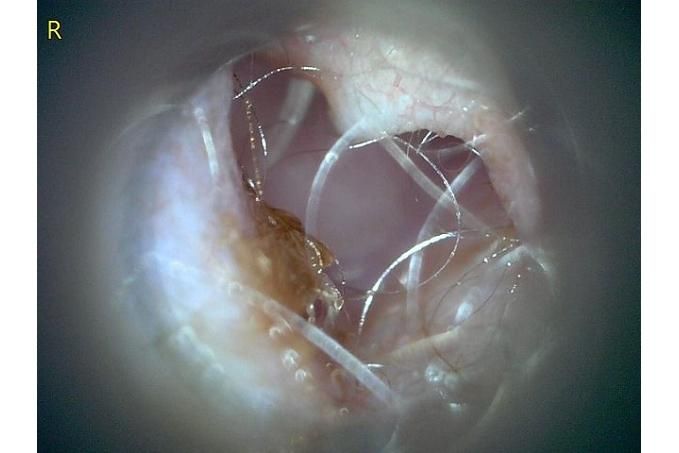

사진만 보고 확진할 수는 없지만 지금 올려주신 귀는 적어도 오른쪽은 정상으로 보이기 어렵습니다 왼쪽은 비교적 연분홍에 가까워 보이지만 오른쪽은 털과 분비물이 많이 차 있고 피부가 자극받은 듯한 모습이라 외이염 가능성을 먼저 생각하게 됩니다 그리고 질문자님이 적어주신 머리 털기 하루 여러 번 귀 만질 때 통증 솜만 닿아도 예민함 귀 긁기 같은 증상은 외이염에서 흔한 신호입니다

다만 이 사진만으로 중이염이나 내이염이라고 단정할 수는 없습니다 중이염이나 내이염은 귀 통증과 머리 털기만으로도 올 수 있지만 보통은 고개 기울어짐 비틀거림 안구가 흔들리는 증상 얼굴 한쪽 처짐 같은 더 깊은 신경 증상이 같이 보일 때 더 의심합니다 지금 적어주신 내용만 보면 제일 먼저는 오른쪽 외이도 염증과 통증 조절이 우선으로 보입니다